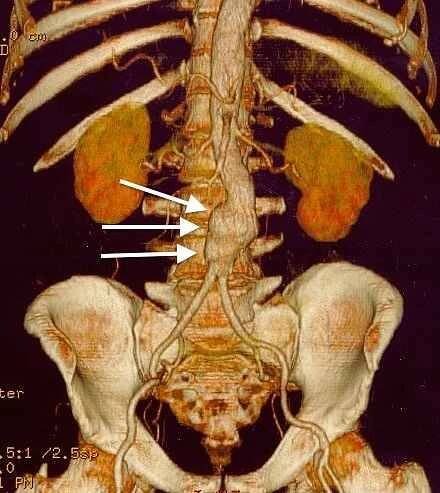

3D rekonstrukce CT skenu aneuryzmatu břišní aorty.